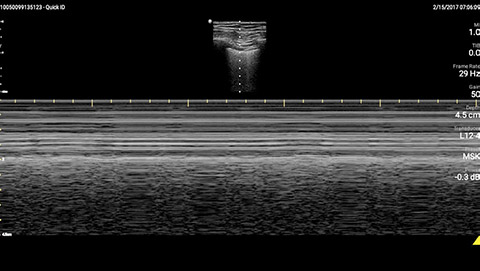

The patient had reduced LV systolic function without new or severe valvular pathology, a dilated, non-collapsing IVC, and diffuse B lines (left greater than right) on lung ultrasound imaging.

M-mode demonstrating lung sliding